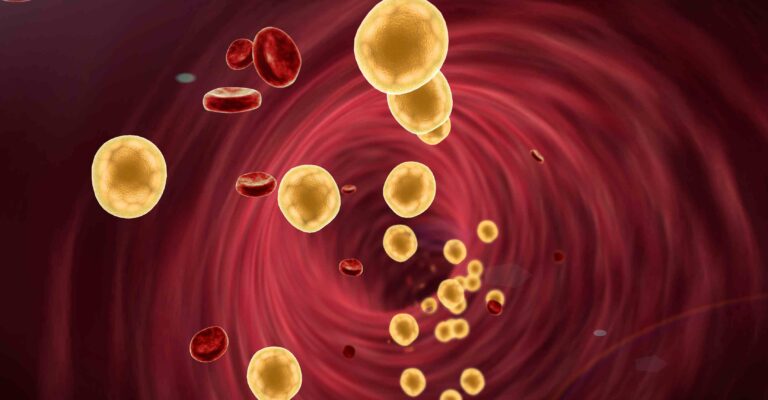

Cholesterol verlagen?

Een hoog cholesterolgehalte in het bloed vergroot je kans op hart- en vaatziekten. Van een hoog cholesterol voel je niets. Daarom is het belangrijk om je cholesterol te laten meten. De meest betrouwbare manier is om dit via de huisarts te doen. Maar ook een gezonde leefstijl helpt je op weg.